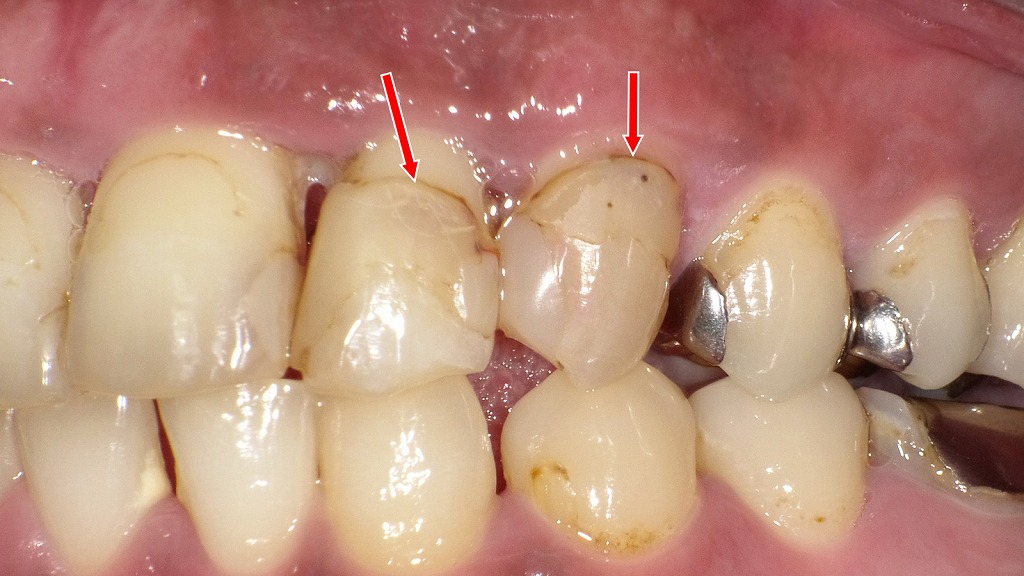

◆ コンポジットレジンの境目が茶色くなる理由|辺縁変色の典型例

赤い矢印の部分に、コンポジットレジン(CR)充填の境目の変色が確認できます。

これは、詰め物自体の変色ではなく、主に以下のような理由で境界(マージン)が着色して見える現象です。

● 辺縁が変色する主な原因

① レジンと歯の境界にできた微小な段差・隙間

年月が経つと、レジンのわずかな摩耗や接着劣化により

**歯とレジンの境目に極細の隙間(マイクロリーケージ)**が生じます。

ここにプラークや着色物が入り込み、茶色〜黒っぽく変色します。

③ 古いレジンの変色・表面粗さの増加

レジンは経年で表面がザラつくため、

色素が付着しやすく、境目から茶色く見えることがあります。